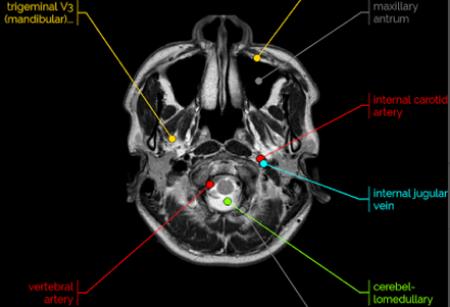

1.可能是人体解剖学图谱最友好、最方便的在线界面之一。包括脑、颞骨/内耳道、鼻咽、眼眶、副鼻窦、颅神经、颞下颌关节、颈部、臂丛、脊柱、肩、臂、肘、前臂、腕、手、手指、拇指、胸/肺、冠状动脉、腹部、骨盆、髋、大腿、膝、腿、踝、足、血管造影等解剖结构。

2.是一款非常实用的医学方面的软件,可以提供给医学生们对人体构造进行详细的学习,人体的穴位可以看的更加清楚,解剖结构更清晰,学习起来也更加的轻松,会在一定程度上提高学习效率。